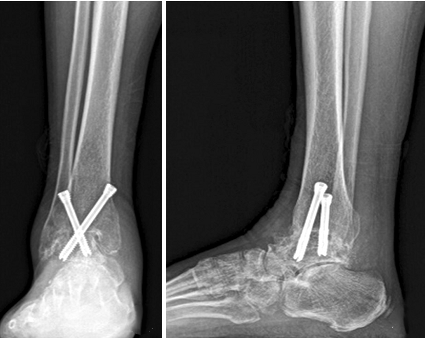

主任,踝关节融合怎么做才最好呀?

主任,踝关节融合怎么做才最好呀?...